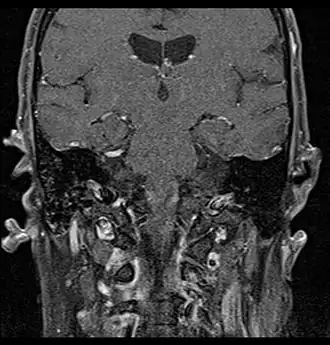

Primary treatment for this cancer, regardless of body site, is surgical removal with clean margins. This surgery can prove challenging in the head and neck region due to this tumor's tendency to show a perineural discontinuous growth, meaning that it follows nerves and different "nests" of the tumor can exist without a connection to the original tumor. Therefore, MRI-images should be analysed following nerve tracts up to the brainstem. Adjuvant or palliative radiotherapy is commonly given following surgery. For advanced major and minor salivary gland tumors that are inoperable, recurrent, or exhibit gross residual disease after surgery, fast neutron therapy is widely regarded as the most effective form of treatment.[13][14][15][16] Chemotherapy is used for metastatic disease. Chemotherapy is considered on a case-by-case basis, as data on the positive effects of chemotherapy are limited. Clinical studies are ongoing, however.

Coronal MRI showing right parotid adenoid cystic carcinoma with perineural spread of tumor: The tumor originates in the right parotid gland and spreads along the trigeminal nerve via the auricuotemporal branch extending intracranially through the foramen ovale at the skull base towards Meckel's cave.

Coronal MRI showing right parotid adenoid cystic carcinoma with perineural spread of tumor along the facial nerve extending to the stylomastoid foramen